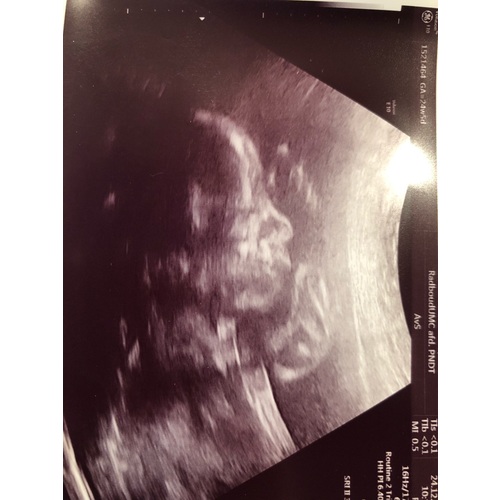

Wat een onwijs duidelijke echo zeg!

Ja eh, ik verschoot er zelf ook van 馃檴

Wauw wat een duidelijke echo! Valt er met 25 weken nog iets van te zeggen? Wij willen het niet weten maar ik ben wel ontzettend benieuwd. 馃槀